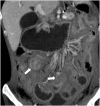

Management of peritoneal surface malignancies is currently entrusted to a multimodality approach. Computed tomography (CT) scan remains the first imaging method despite the limitations in identifying small implants in critical regions. Magnetic resonance imaging is usually recommended for its performance in small implants, mesentery, and small bowel assessment. Positron emission tomography/CT plays an important role only in pseudomyxoma peritonei. Thus, becoming aware of the imaging strengths and drawbacks and having a multimodality imaging approach might be the best option for the patients.